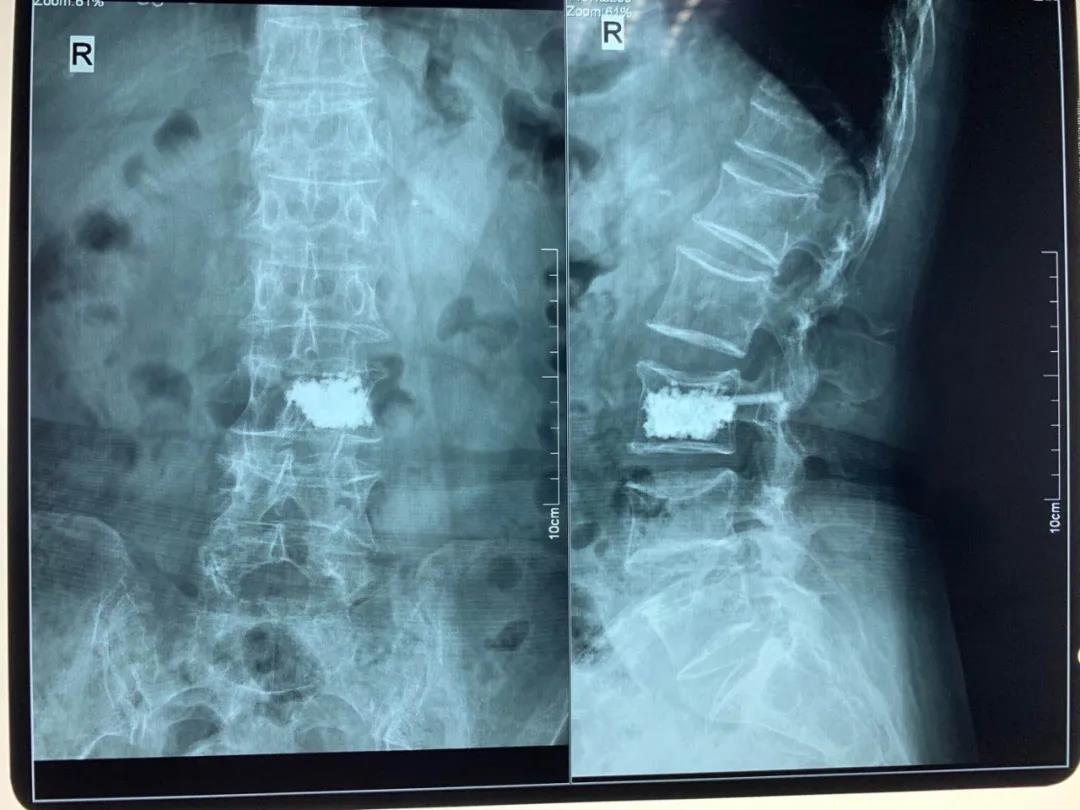

椎体骨折

青壮年椎体骨折无神经压迫症状骨二科采用微创经皮椎弓根螺钉内固定术,避免了手术大切口引起的椎旁肌破坏,老年骨质疏松性椎体压缩骨折骨二科采用局麻下经皮椎体成形术(PVP、PKP)术,术后患者即可解除疼痛,第二天恢复正常生活。

pvp